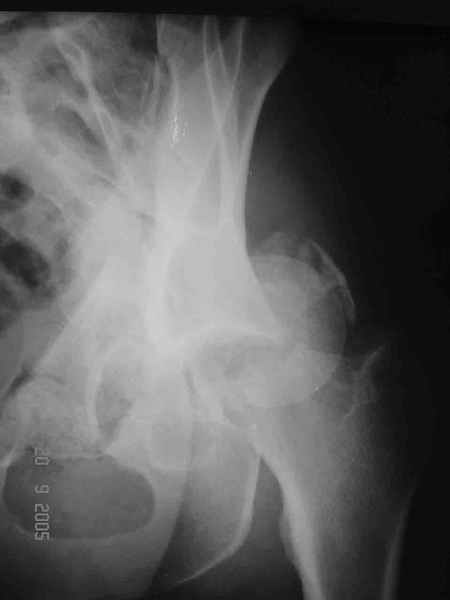

Привет! Вот недавно прооперировали похожий на ваш случай - впадина + шейка (правда у нас впадина поперечный+задний край). После травмы прошло 4 недели. мужчине 46 лет. С такой комбинацией все показания к первичному протезированию. Морально и технически мы к этому уже созрели.Но больной не собрал денег на протез. Выполнили остеосинтез впадины и шейки, прекрасно понимая, что головка вскоре рассосется, мы хотя бы надемся что к этому времени таз срастется, как говорится создали все условия для дальнейшего протезирования (может, и протез в последующем подешевле будет, в смысле, без укрепляющего кольца?). Привет Рункову!

Привет Алекей! Сделано неплохо, поздравляю, хотя второй винтик можно было бы и подлиннее в шейку загнать! Пара вопроов: доступ такой же? головка была свободной или висела на капсуле?

Согласен, можно было и подлиннее. Доступ такой же - чрезвертельный, только разрез кожи прямой (а не Y, чего то я разницы не ощущаю). Головка была абсолютно свободной (то есть во время остеосинтеза таза лежала в стакане и не мешалась). Шансов, что она прирастет 0,00001%. Хотели даже выбросить, но привинтили как временный биологический протез (читай свободный трансплантат), чтоб на период срастания таза бедро проксимально не ушло (может ортопеды потом спасибо скажут). Ну а у вас первичное протезирование при переломе впадины тоже пока полько в планах?